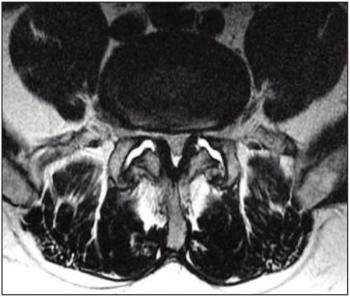

Large numbers of perivascular spaces seen in the brain are more commonly found in patients who go on to develop cognitive problems or dementia.